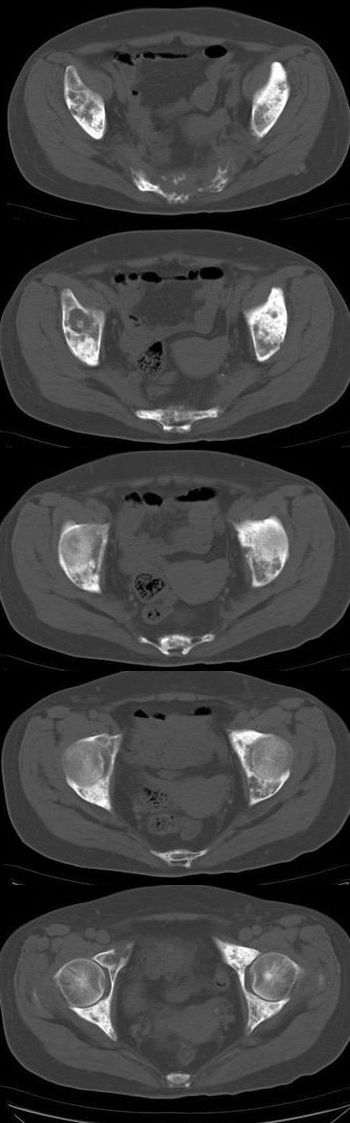

标题: CT13121:女,54岁。乳腺癌术后8年。 [打印本页]

女,54岁。乳腺癌术后8年。现感觉左腿酸困不适,并向下放散。左腿僵硬,不由自主。

典型溶骨型转移瘤。

骨盆及腰椎多发性溶骨性转移瘤.

成骨及融骨转移。

结合病史考虑乳腺癌术后多骨骨转移。

患者臀部皮下脂肪、筋膜、臀大肌处多个小结节、钙化影,看来挨了不少肌肉注射的苦头

支持 骨转移瘤---混合型以溶骨为主

结合临床考虑多骨多灶性溶、成骨性转移。